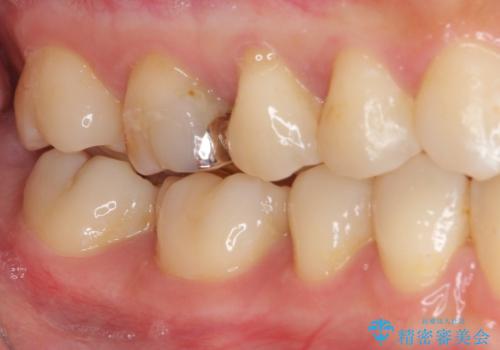

処置後に痛みを感じることはなく、冷たいものがしみることもなくなりました。

奥の大臼歯にもむし歯があったので、一緒に処置を行いました。